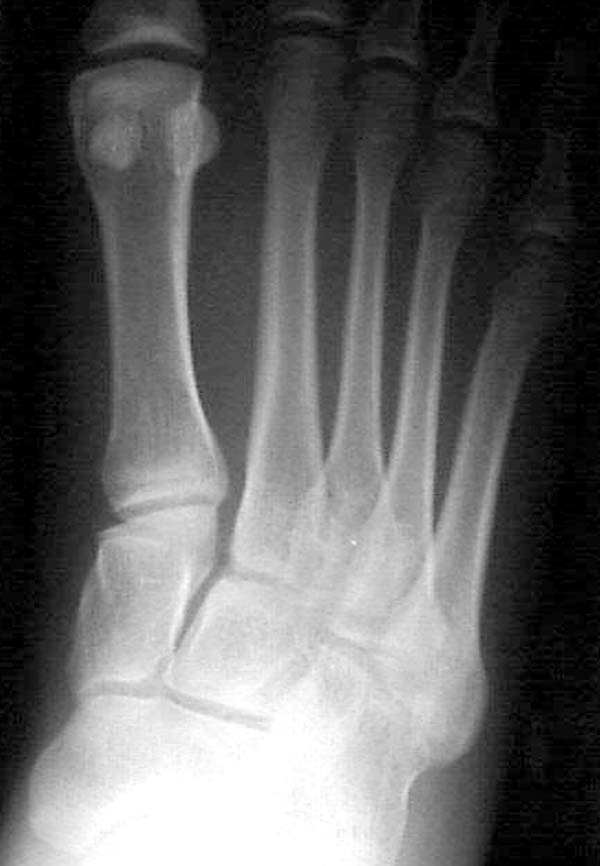

Здесь КТ и сравнительные снимки стопы под нагрузкой.

Диагностировано повреждение медиальной и латеральной колонны.